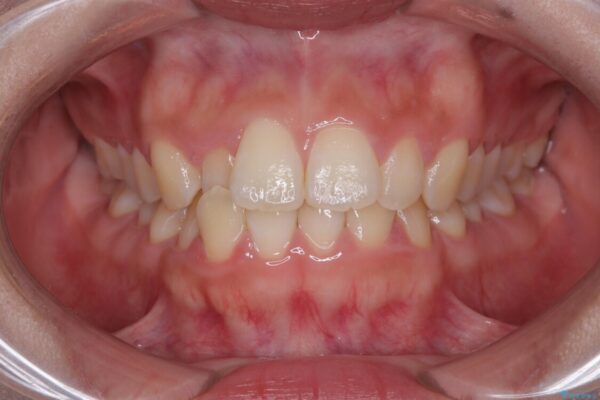

前歯のデコボコが気になるでのことで来院された患者様です。

歯列アーチが狭くスペース不足により前歯がデコボコしている状態でした。見た目を改善しつつ、前歯を前方に突出させず、自然な笑顔を目指したいというご希望でした。

治療前

• 目立ちにくい表側装置で1年完了!狭いアーチを側方拡大し前歯のデコボコを整えた症例 治療前画像